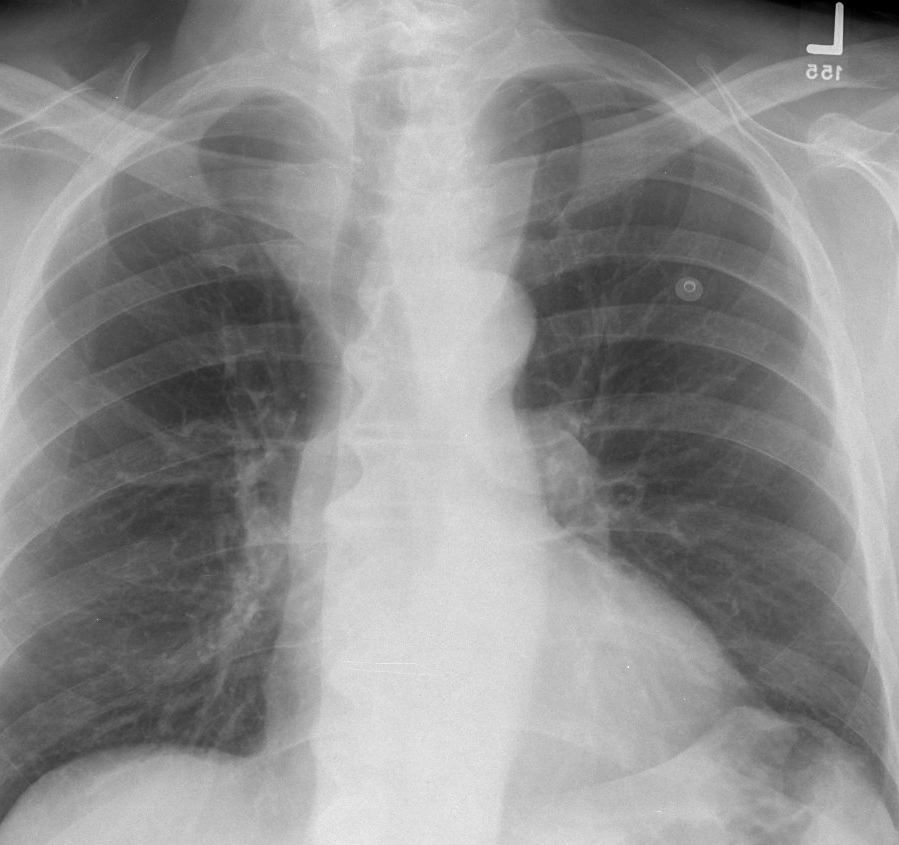

Thyroid Mass

Case 8 PA